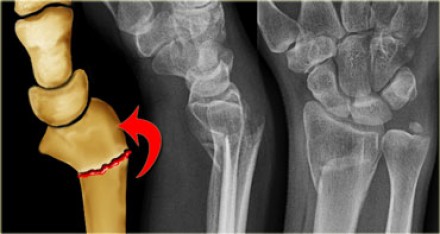

The most common cause of spinal fractures and dislocations in India is road traffic accidents followed by fall from height (usually a fall from tree). Spinal fractures can damage the spinal cord, resulting in paralysis. This paralysis can be permanent, and have devastating consequences on the patient and his family.

Some of these patients may need a Spine Surgery to fix these fractures. This may be done using plates or rods and screws made of Titanium. Some of these fractures can be fixed using Minimally Invasive Spine Surgery (MISS).

Patients with ankylosing spondylitis and osteoporosis are also predisposed to developing spinal fractures even with trivial trauma like a fall at home or a slip in the bathroom